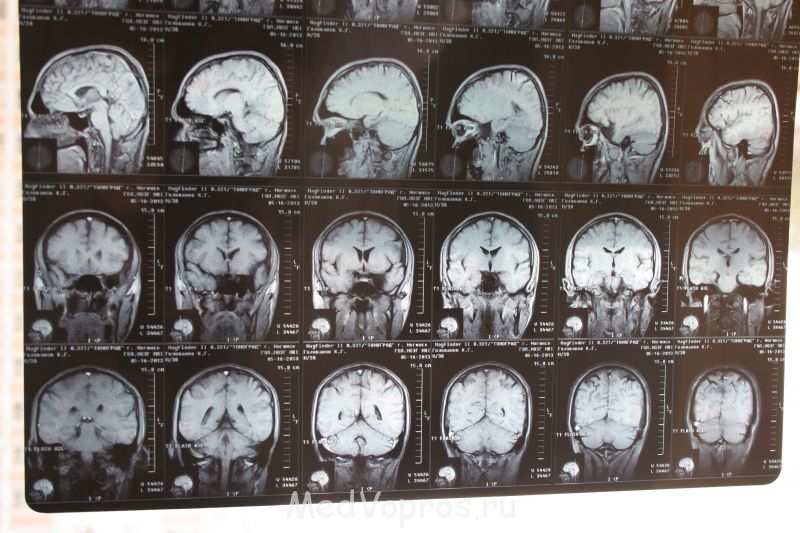

Здравствуйте!!! Моему супругу 37 лет. Его беспокоят частые головокружения и пелена в левом глазу (был у окулиста, сказали что с глазом все в порядке, отправили к невропатологу) Невропатолог назначил диагностику МРТ головного мозга и сосудов. МРТ показало, что никаких патологий не выявлено и сосуды в порядке, но есть арахноидальная киста левой височной доли (в районе левого глаза) размером- 40*20*29 мм. Скажите, пожалуйста, как избавиться от кисты без операции? Может ли она рассосаться или уменьшиться в размерах при принятии лекарств? Какое еще можно сделать обследование и какие сдать анализы, что бы понять причину образования кисты? P.S. в возрасте 17 лет было сотрясение головного мозга с кратковременной потерей сознания, в возрасте 13 лет были 2 приступа продолжительностью 30 минут сопровождающиеся онемением конечностей, несвязной речью, путаностью мыслей и головокружением.